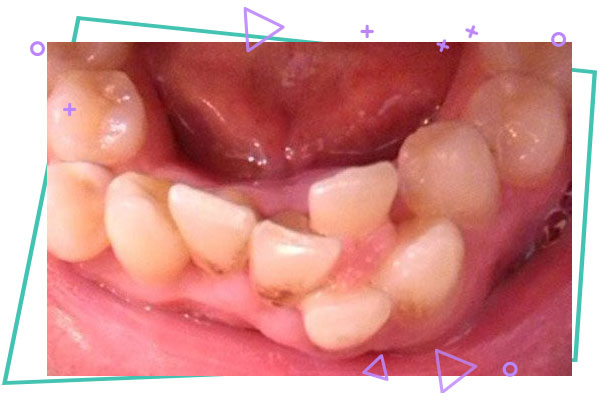

مشکلات ناهنجاری های فک و دندان به دو دسته ژنتیکی و محیطی تقسیم بندی می گردند . در عامل ژنتیکی ، کوچک بودن نسبت فک به دندان ها ، شلوغی و به هم ریختگی دندان ها را به همراه دارد و در بزرگ بودن آن ، ایجاد فاصله بین دندان ها مشاهده می گردد. از عوامل محیطی می توان به از دست رفتن زودهنگام دندان های شیری، عادات دهانی مضر مثل مکیدن انگشت یا قرار دادن اشیا بین دندان ها و وجود لوزه های متورم اشاره کرد.

۱ : وجود لبخند و ظاهری نازیبا که گاهی باعث کم شدن اعتماد به نفس و مشکلات در ارتباط با افراد می گردد .

۲ : احتمال افزایش شکستگی دندان های بیرون زده

۳ : افزایش پوسیدگی به علت کج بودن دندان ها ، گیر غذایی و تمیز نشدن آن ها ، احتمال ایجاد بیماری های لثه به علت کج بودن دندان ها ، تمیزنشدن دندان و لثه و ایجاد بوی بد دهان به علت تجمع مواد غذایی

۴ : اختلال در جویدن و بلع غذا

۵ : ایجاد تکلم نادرست

۶ : احتمال ایجاد مشکلات مفاصل فکی